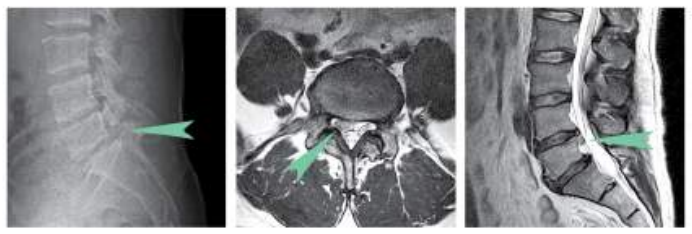

▲ 40~50대 허리디스크 및 협착증 치료

평소 골프를 즐겨 치시는 50대 환자 분의 케이스입니다. 골프를 칠 때 지속적으로 느껴지는 요통으로 인해 검진 차 콕통증의학과를 찾아주셨습니다.

환자 분께서 호소하시는 증상은 심각하지 않았지만 X-Ray 상에는 이미 요추 4번-5번과 요추 5-천추 1번 추간판 탈출증 및 협착증, 척추 분리증까지 보이는 상태였습니다. 특히 척추 분리증은 수술을 필요로 할 수 있어 몹시 당황하셨습니다. 하지만 아직 젊은 연세인 데다 한창 사회생활을 하고 있어 수술에 부담을 느끼셨습니다.

콕통증의학과에서 CI 치료를 3차까지 진행하신 결과 많이 호전되어 자가 운동을 통해 허리 관리를 해오셨습니다.

twi001t2039977.jpg

그러던 중, 6개월 후 급성통증으로 다시 내원하셨습니다. 골프를 치는 도중 참을 수 없는 극심한 허리 통증을 느낀 후 바로 병원을 찾으셨습니다. 바로 MRI 촬영을 진행하였고 신경관이 많이 눌린 상태를 확인할 수 있었습니다. CI 시술 1회 차를 더 진행하였으며 꾸준한 운동치료로 관리 중에 있습니다.

골프는 허리디스크, 척추 분리증 환자에게 맞지 않는 운동으로 제대로 관리를 하지 못할 경우, 본 환자분처럼 재발을 불러올 가능성이 높습니다. 신경 주사 치료 외에도 환자의 평소 생활습관, 자세 등을 고려한 전문 운동 치료가 필요한 이유입니다.